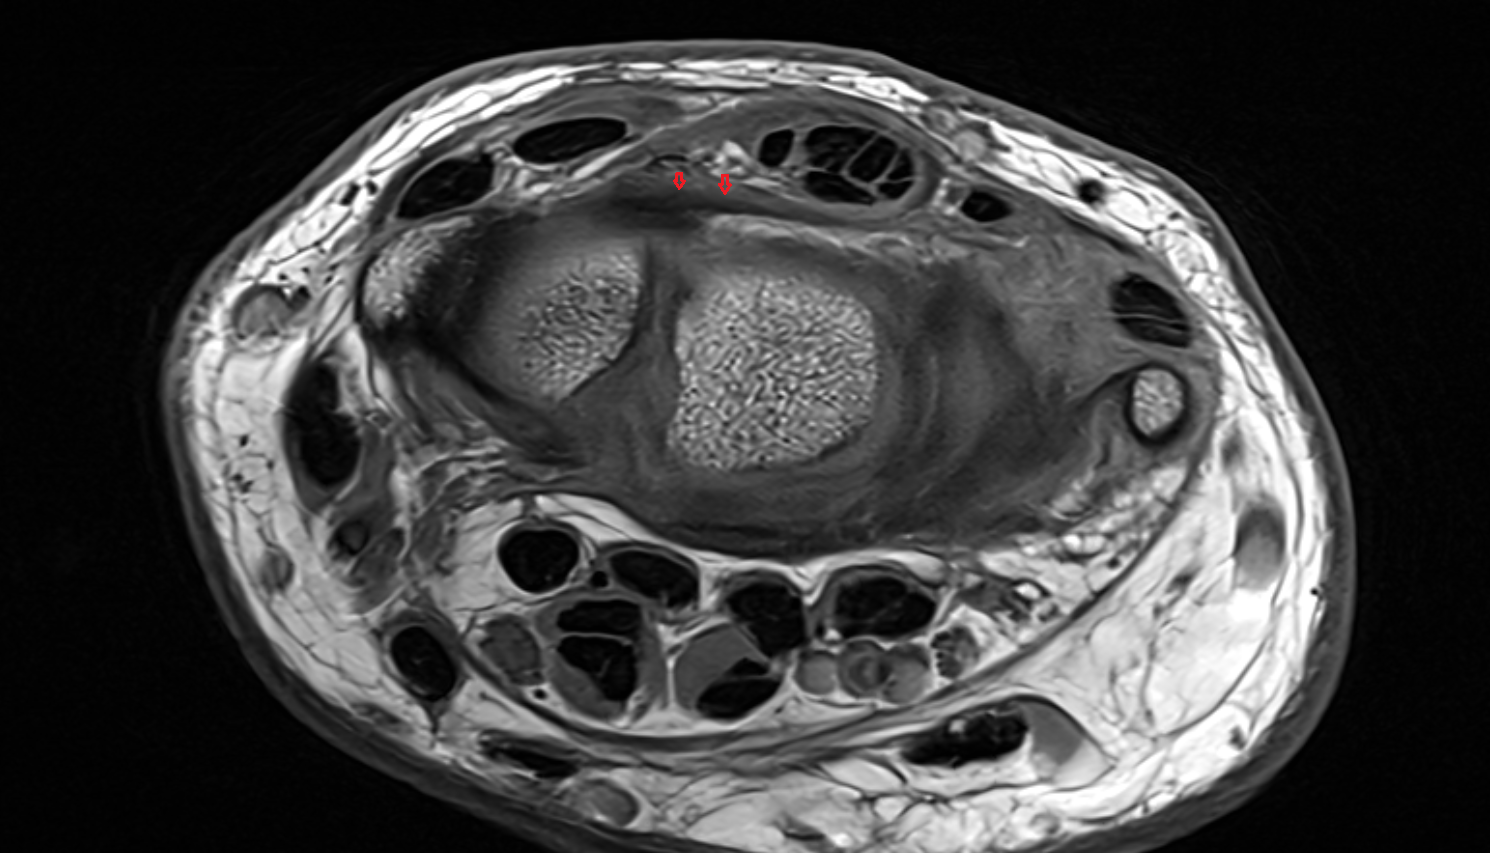

- Knee Joint